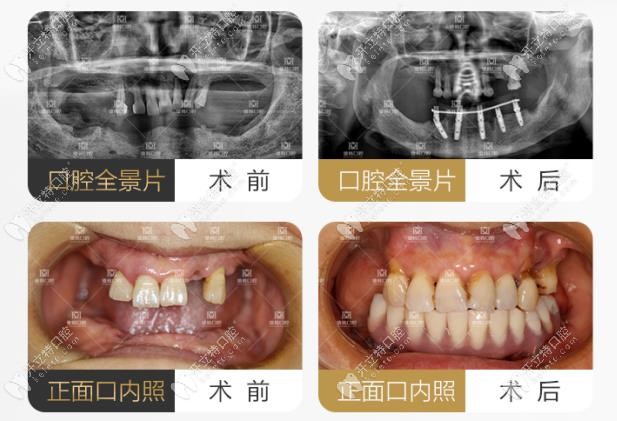

上下頜牙齒松動(dòng),采用all-on-4做全口即刻負(fù)重案例

案例主角是一位78歲的高齡患者,因?yàn)槿谏舷骂M牙齒全部松動(dòng),由于常年佩戴假牙,導(dǎo)致牙槽骨也出現(xiàn)了重度萎縮,咀嚼功能受限,特到院內(nèi)檢查。

羅薩蒂提出方案為:上下頜松動(dòng)的牙齒及殘根全部拔除,采用all-on-4進(jìn)行全口即刻負(fù)重技術(shù)進(jìn)行當(dāng)天佩戴牙冠。

羅薩蒂做all-on-4案例圖

手術(shù)當(dāng)天,羅薩蒂先將殘根拔除,然后根據(jù)顧客牙槽骨條件,植入植體,當(dāng)天下午就佩戴上牙冠,完成修復(fù)。